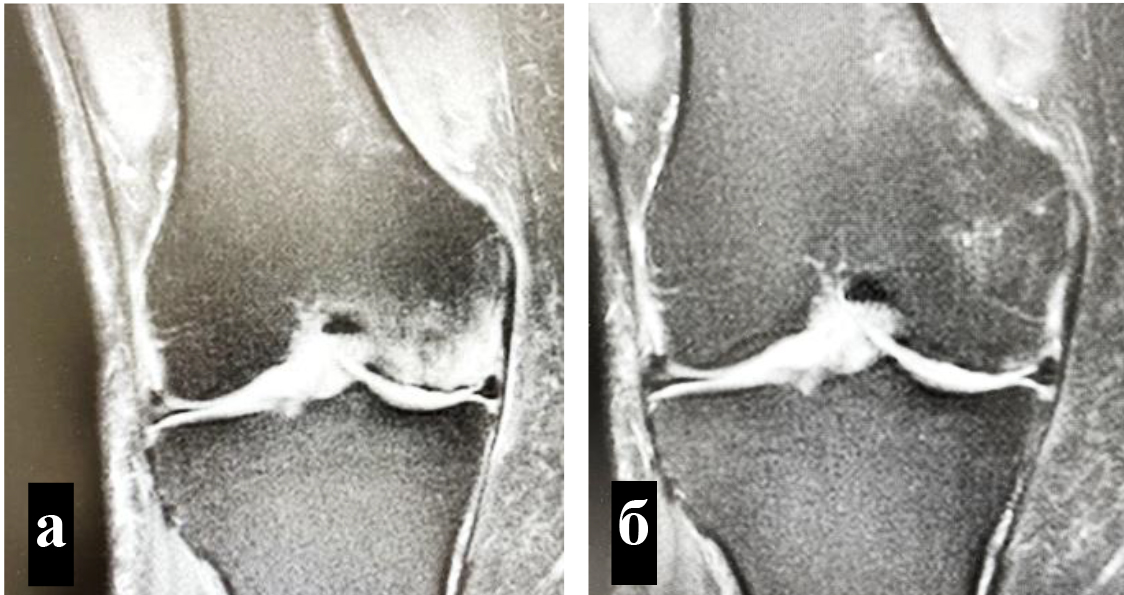

Техника подготовки препарата и инъекции. Забор крови и приготовление ОТП выполняли в условиях процедурного кабинета или перевязочной при соблюдении необходимых правил асептики и антисептики. Согласно методике YCELLBIO PRP (Корея), двухкратно центрифугировали кровь пациента и получали 3 мл ОТП, которую центрировали в узком перешейке пробирки и забирали при помощи шприца (рис. 2) Количество тромбоцитов в готовом препарате составляло 962 ± 40 × 109/л.